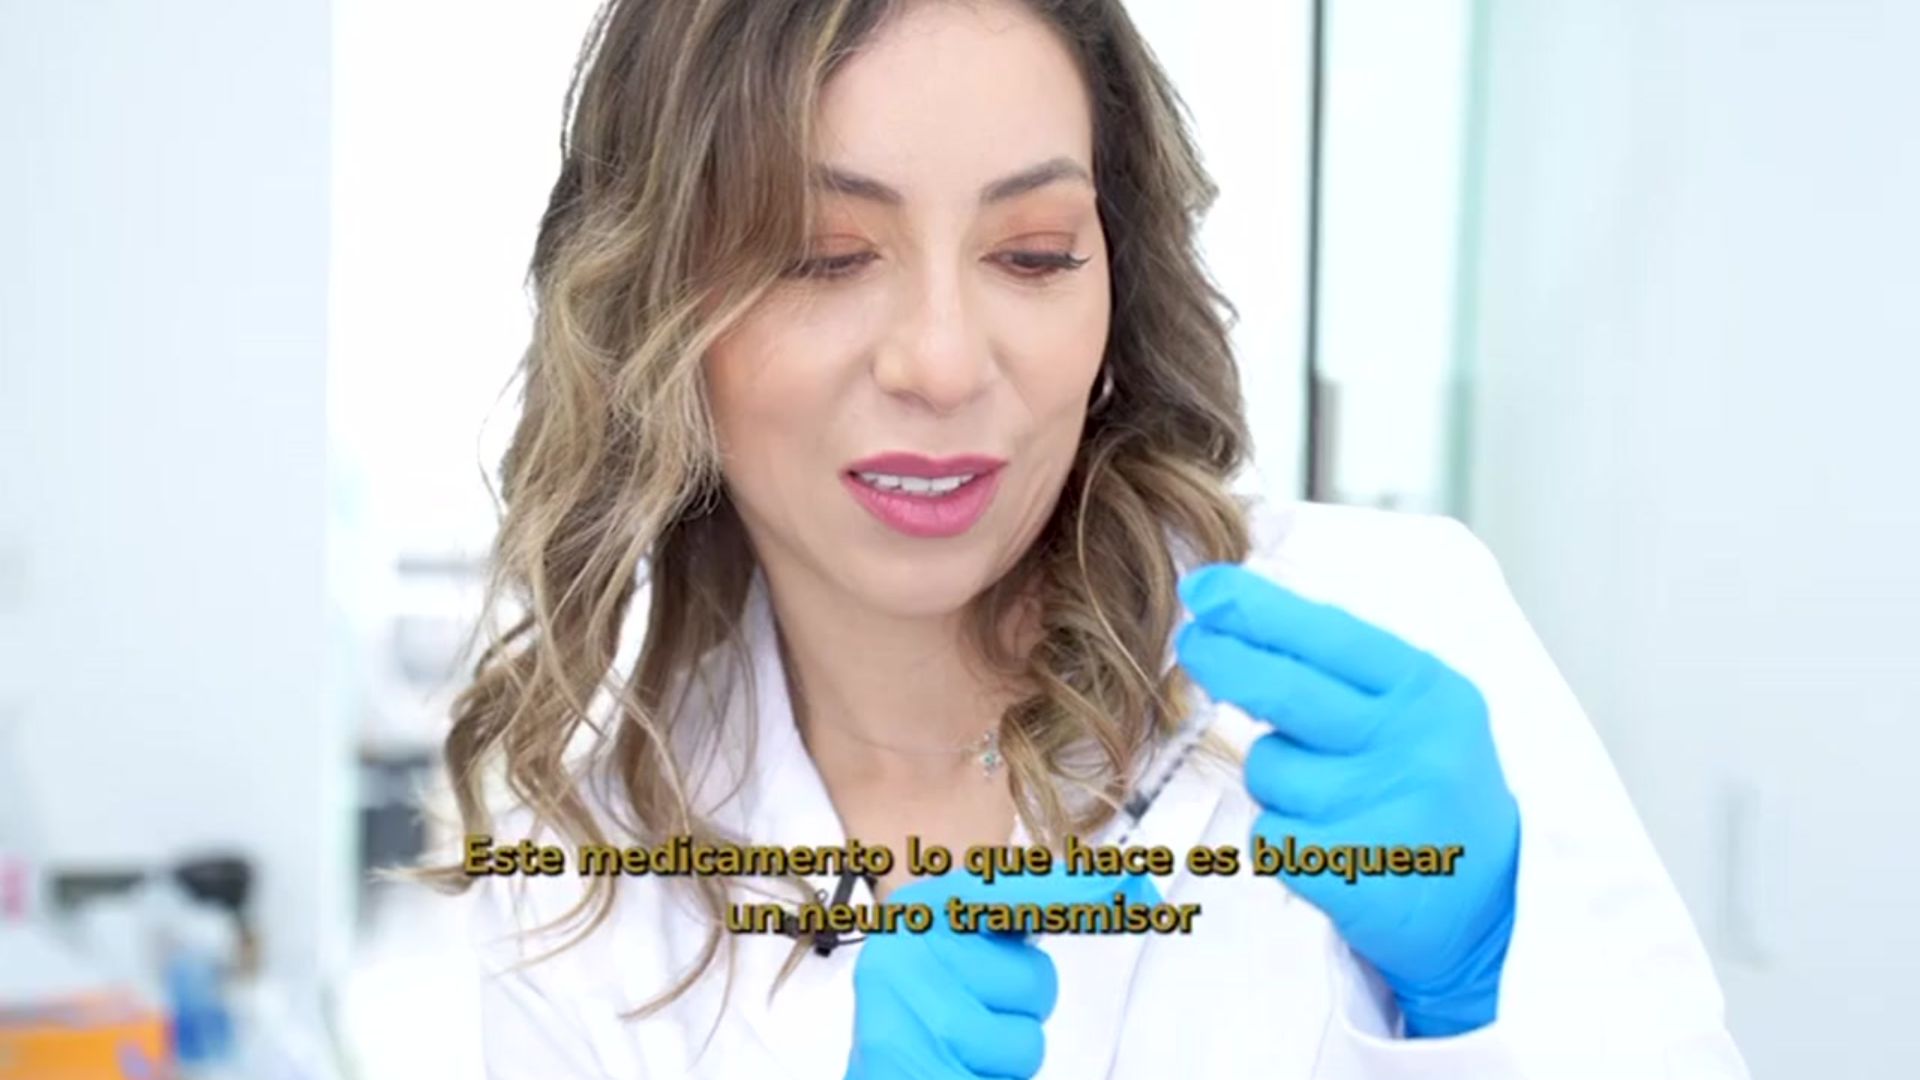

Somos expertosen el cuidado y tratamiento médico, quirúrgico y estético de la piel de hombres, mujeres, niños y personas de la tercera edad.

Tratamientos Dermatológicos

Dermatológia Estética